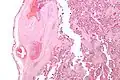

It can be diagnosed by histomorphologic examination of the placenta and is characterized by fetal vessel thrombosis and clustered fibrotic chorionic villi without blood vessels.

Low mag. -